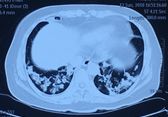

患者2018年6月10日自觉受凉后出现发热,体温最高39℃,无畏寒寒战、咳嗽咳痰等不适,就诊外院查血常规:WBC 7.1×109/L,NEUT# 6.42×109/L,NE 90.4%,Hb 93g/L,血气分析(未吸氧):PH 7.50,pCO2 33.7mmHg,pO2 69mmHg,HCO3- 26.1mmol/L,胸部CT提示右中叶实变、双下肺支气管血管束周围结节样实变影。(如图1)

图1:胸部CT(2018年6月12日)